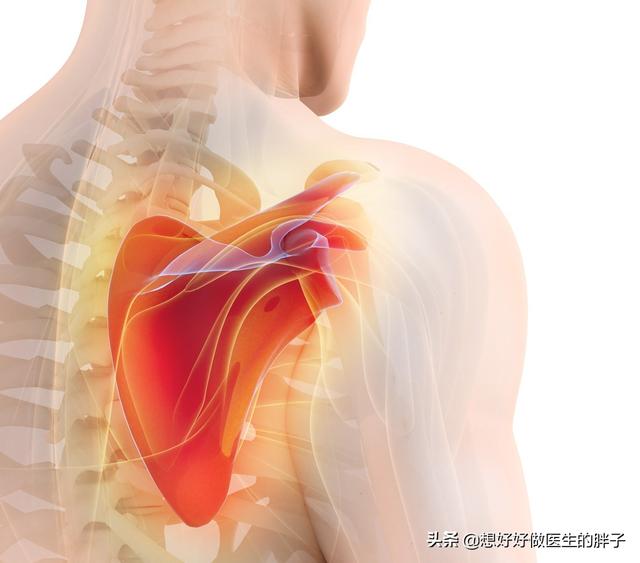

En ce qui concerne la douleur de l'omoplate droite, en tant que cardiologue, il est toujours nécessaire de répondre à cette question, car la douleur de l'omoplate dans le dos est parfois liée au cœur, mais on ne peut pas dire que la douleur de l'omoplate dans le dos est nécessairement une maladie cardiaque, on peut seulement dire que la maladie la plus terrible pour la douleur de l'omoplate dans le dos est une maladie cardiaque, et aujourd'hui, le Dr Zhang est ici pour vous expliquer ce problème.

De nos jours, la première chose qui vient à l'esprit de nombreuses personnes est la maladie cardiaque, en particulier la maladie coronarienne et l'infarctus du myocarde. Cela montre que le niveau de connaissances en matière de santé de l'ensemble de la population est élevé et que les gens peuvent penser à des maladies graves par le biais de certains symptômes atypiques. Mais pour être honnête, la plupart des patients souffrant de douleurs aux omoplates ne sont pas atteints d'une maladie coronarienne, ni d'un infarctus aigu du myocarde, qui peut être une maladie coronarienne, l'infarctus du myocarde ne peut être considéré que comme un très petit nombre de cas. Alors, quelle douleur au niveau de l'omoplate doit-on considérer comme une maladie coronarienne ?

Tout d'abord, ce type de patients doit présenter des facteurs de risque de maladie coronarienne, tels qu'un diabète sucré de longue durée, une hyperlipidémie, etc. En même temps, ce type de douleur scapulaire est souvent lié à l'activité physique ou à l'excitation émotionnelle, et s'accompagne souvent d'une gêne thoracique antérieure, telle qu'une douleur thoracique, une oppression thoracique et d'autres gênes, qui dure quelques minutes et peut être soulagée par le repos ou l'administration de nitroglycérine ; il ne s'agit pas d'une gêne scapulaire qui dure quelques jours, comme c'est le cas chez de nombreuses personnes qui ne sont pas soulagées de façon persistante. Soulagement.

Deuxièmement, si l'on soupçonne fortement que cette douleur scapulaire intermédiaire est une douleur irradiante d'ischémie myocardique, un ECG peut être réalisé au moment de l'apparition de la gêne, et si l'ECG suggère la présence d'une ischémie myocardique, il convient d'envisager d'autres examens. Si l'électrocardiogramme ne suggère pas la présence d'une ischémie myocardique et qu'il n'y a pas beaucoup de facteurs de risque de maladie coronarienne, il vaut mieux envisager de vérifier la tension musculaire, la spondylose cervicale et d'autres maladies diverses qui causent des douleurs scapulaires, ne pas mettre toute son énergie sur le cœur ou la maladie coronarienne.

Enfin, le Dr Zhang aimerait rappeler à tout le monde qu'il existe des milliers de maladies pouvant causer des douleurs à l'omoplate, telles que la spondylose cervicale, la neuropathie musculaire, etc. Et si cette douleur de l'omoplate suggère, par le biais de diverses méthodes, l'existence d'une possibilité d'ischémie myocardique, il convient alors de se rendre au service de cardiologie, d'essayer de procéder à une détection précoce, le traitement précoce étant plus efficace.

Même dans certains cas, une maladie coronarienne, un infarctus du myocarde peuvent également se manifester par une certaine douleur scapulaire, bien que relativement rare, mais qui ne peut être totalement exclue, ce qui nécessite de se rendre à l'hôpital pour y subir un électrocardiogramme.